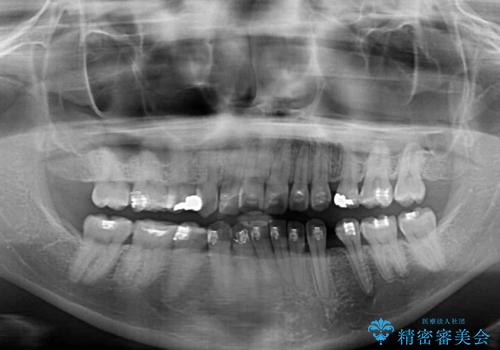

- 海外で抜歯矯正を開始し、治療途中で帰国したため、転院先を探しているとのことで来院された患者様です。

ワイヤーは抜けてしまい、後戻りが始まっている状態でしたが、既存の装置を継続利用して受け入れてくれる医院が見つからないとのことでした。

当院では、張り替える必要のある部位は張り替えることで継続することとし、抜歯スペースを閉じていくように治療を行うこととしました。

後戻りにリカバリーに少し時間を要しましたが、1年強の期間で無事に治療を終えることができました。